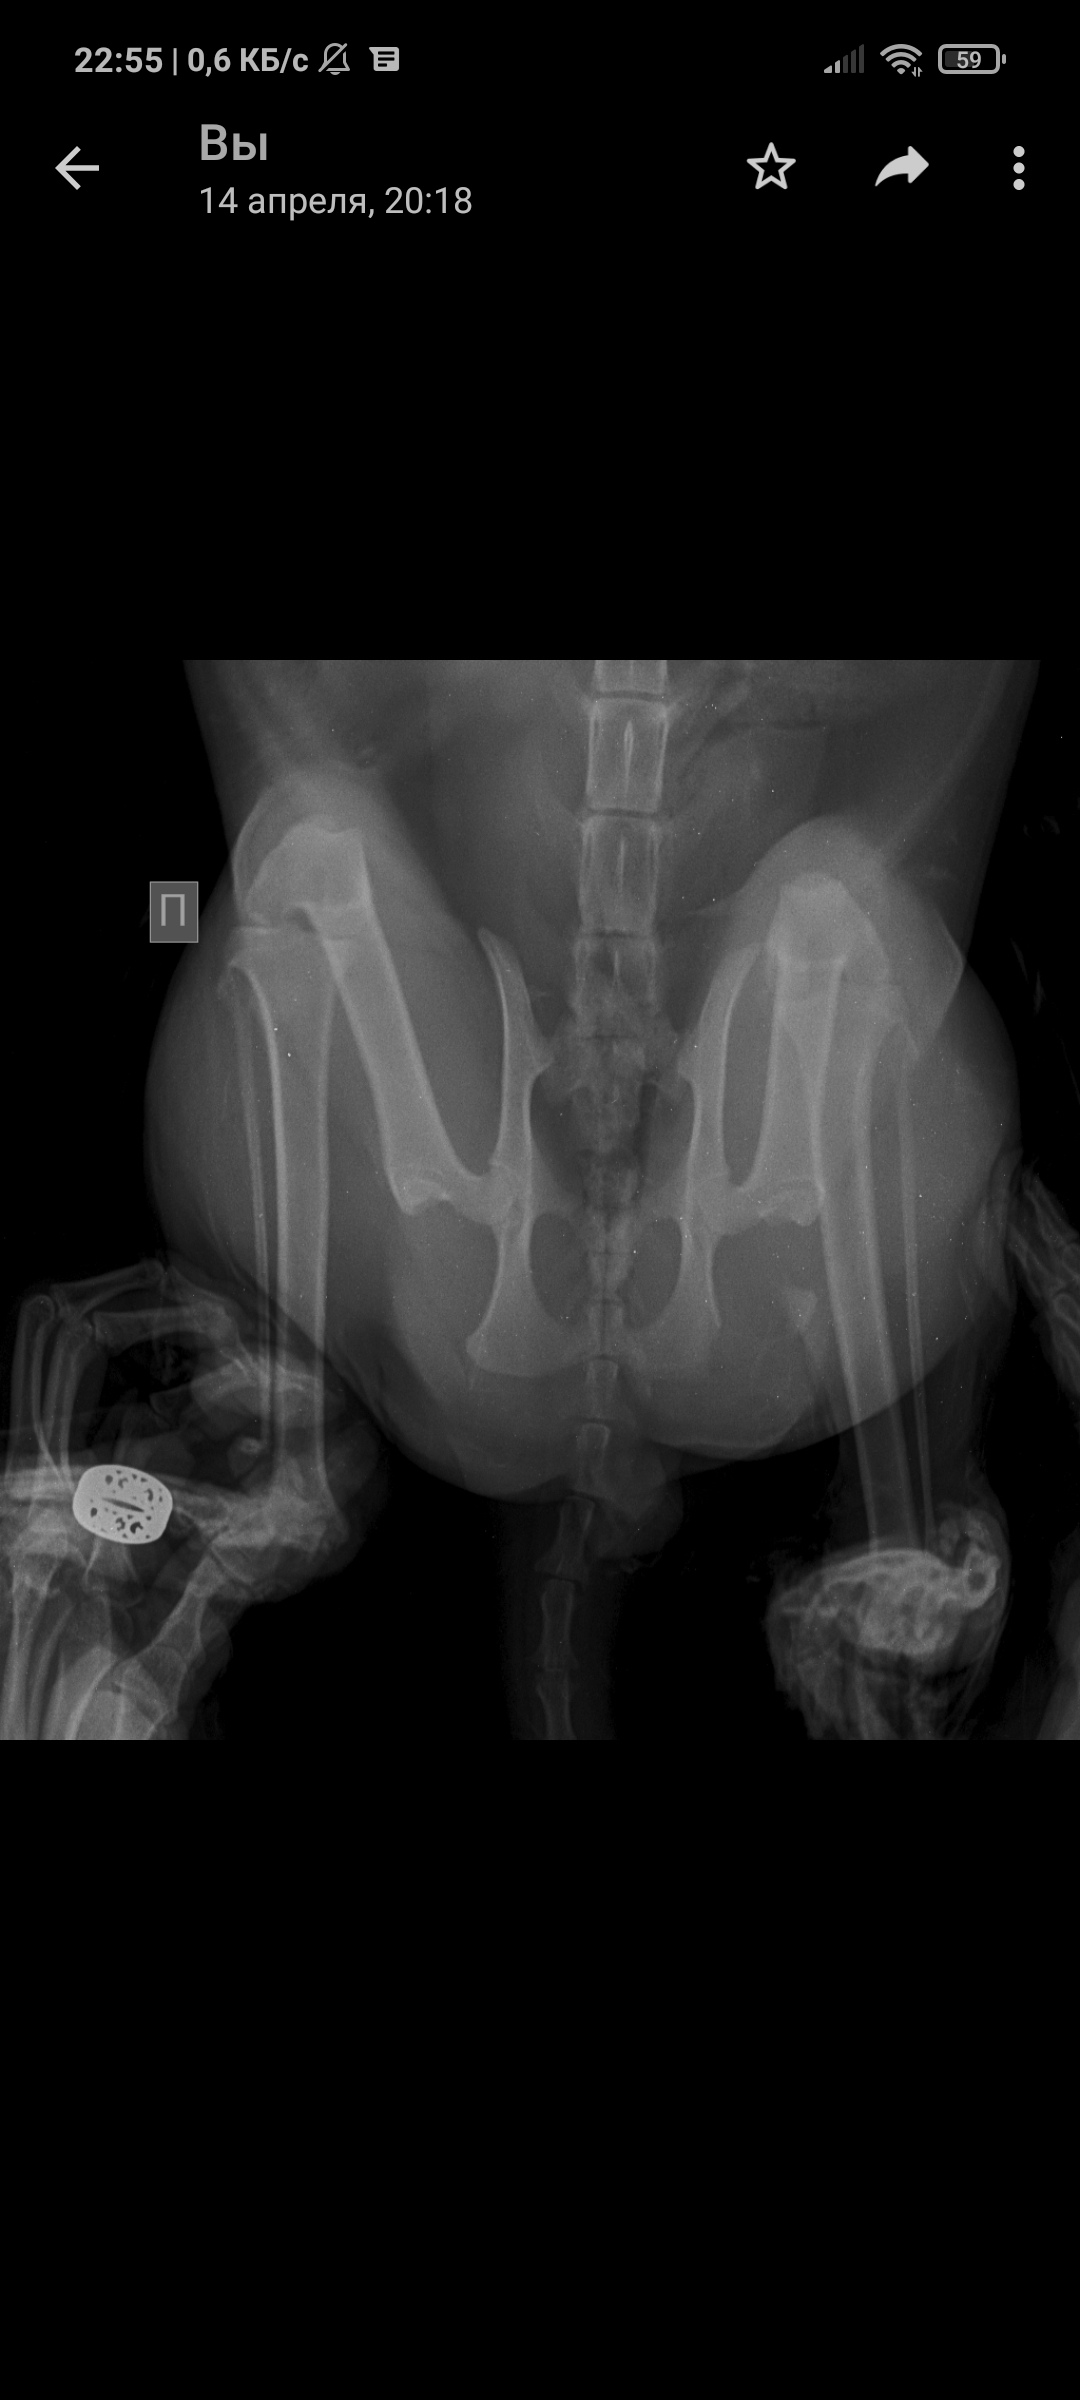

Так уж получилось что я ветеринарный врач, работаю в интенсивной терапии - принимаю и лечу самых тяжелых животных. На днях ближе к ночи прибегает женщина с котом, который шлёпнулся перед ней на улице. При осмотре выясняется что кот в шоке - лежит на боку, без давления, температуры, у него сломаны передние лапы, лицо, пневмоторакс и немного жидкости в брюшной полости (вероятно кровь). Женщина оставляет двадцатку на первые сутки и идет искать хозяина, кот помещается в стационар для стабилизации состояния. Всю ночь я ебусь с этим котом, вывожу его из шока, спускаю ему пневмоторакс, грею, обезболы льются рекой, к утру кот похож на кота, а не на покойника - начал садиться, ползать, полизал еду.

В общем, четвертый день от падения, полет нормальный, кот начал есть сам, а я иду на смену, ждите новостей, думаю скоро будет пост про то, как мы оперируем животных, в частности собираем ходули герою этой истории 😁